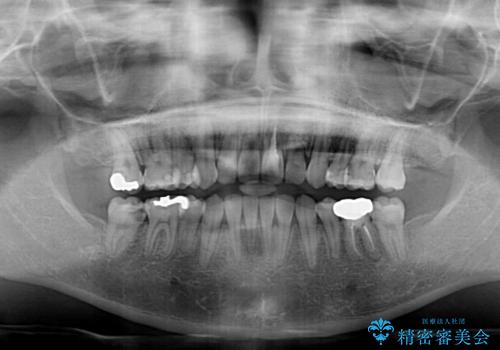

治療は順調に進み、予定された期間で終了することができました。

装置除去後には、スッキリとした口元となり、大変満足していただきました。